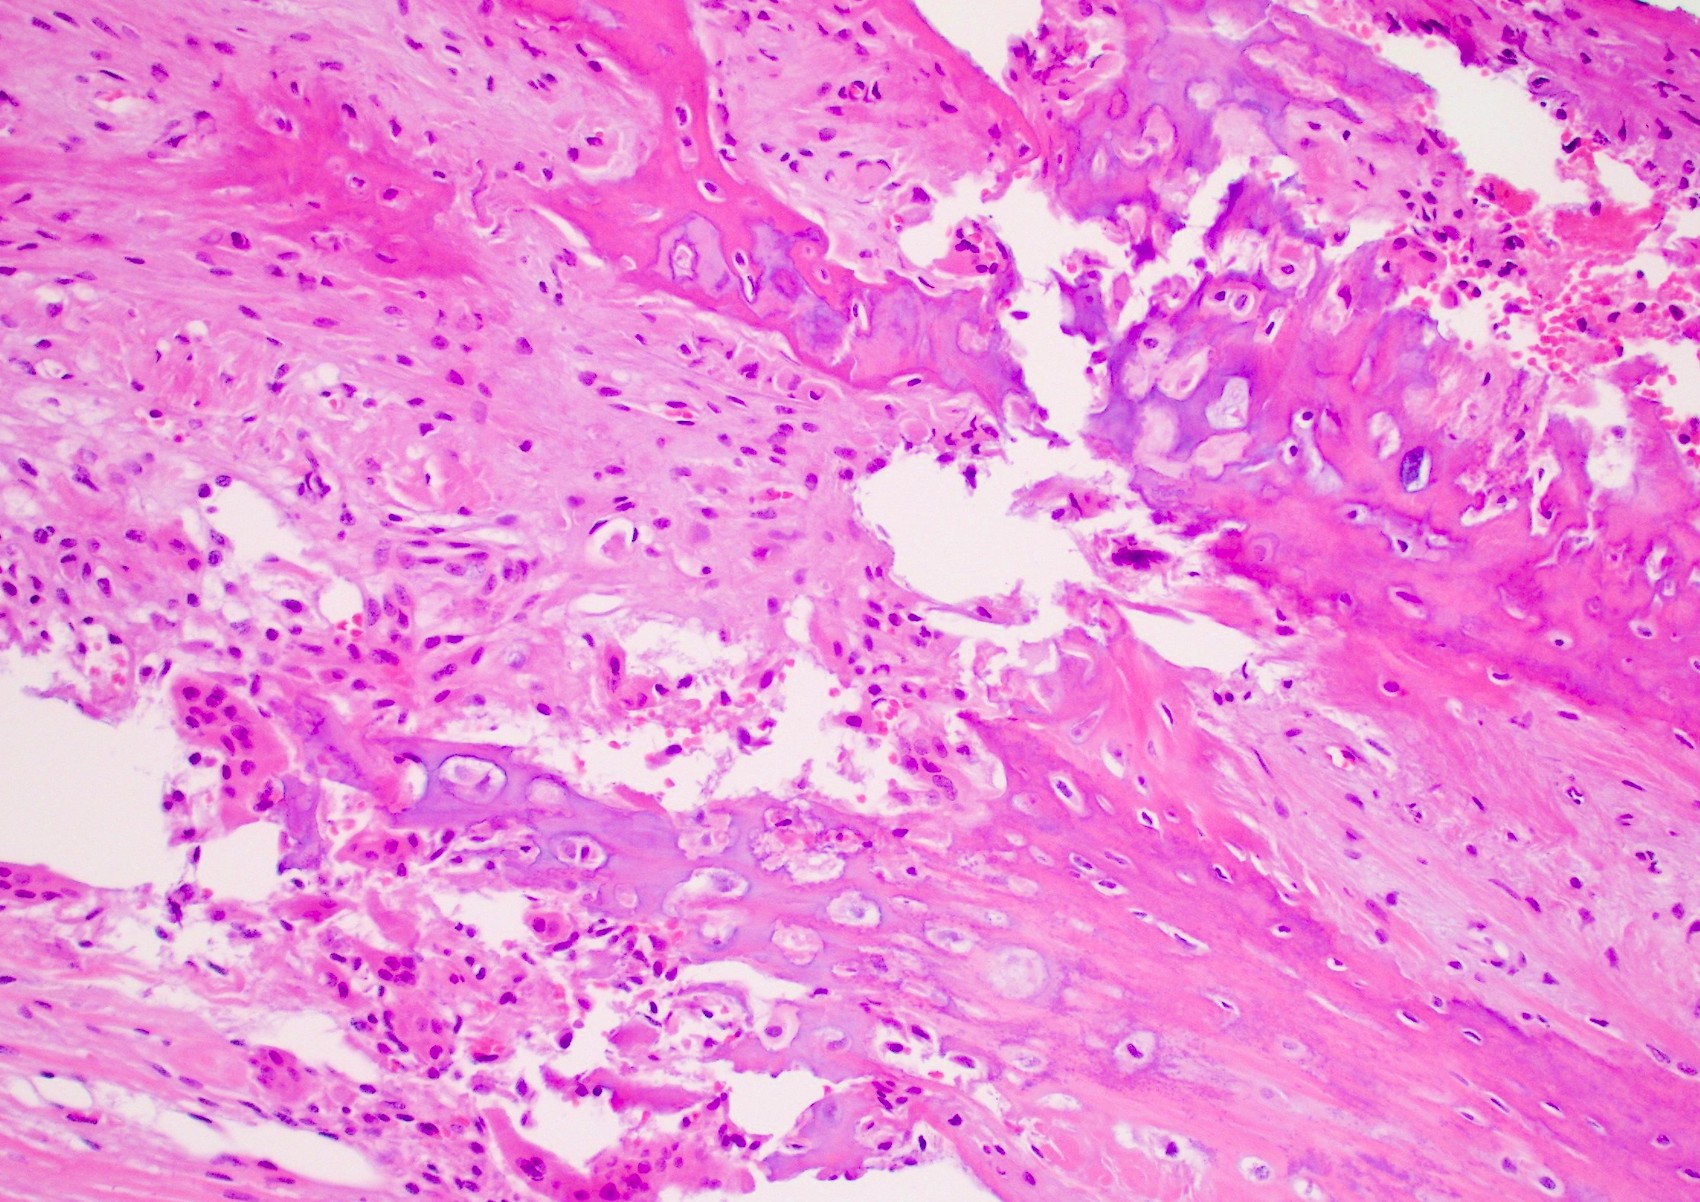

Histologic section of fracture site during the early, fibrous callus Corn Callus Pathology Outlines Callus shows a markedly dense, usually orthokeratotic stratum corneum underlain by mild acathosis, variable hypergranulosis, and increased collagenization of. Plantar warts are mostly endophytic and show multiple deep extensions of acanthotic epidermis around a central parakeratotic plug. These forces result in hyperkeratosis, clinically and histologically. Corns and calluses are thickened areas of skin due to repeated pressure, friction, or irritation.. Corn Callus Pathology Outlines.